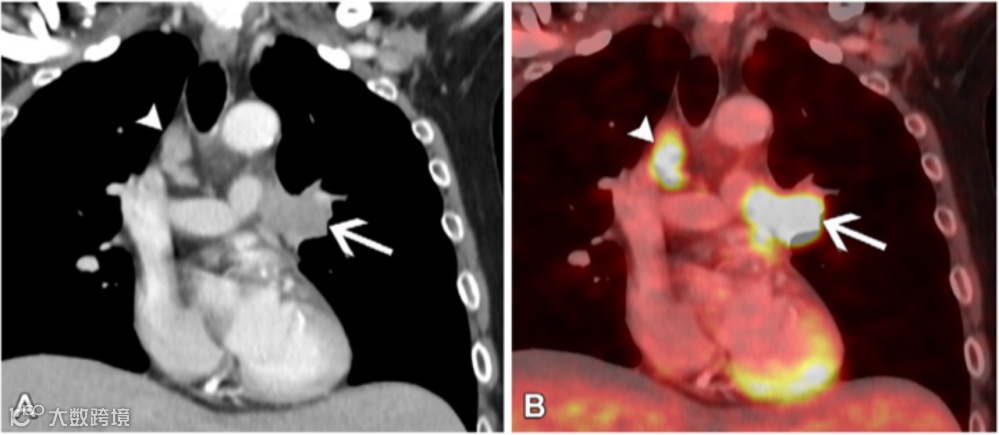

图11.两例N3期病变患者。

(A,B)63岁女性非小细胞肺癌(NSCLC)患者的冠状重建增强胸部CT图像(软组织窗)(A)显示左上叶原发肿瘤(箭头)直接侵犯左肺门,并且在对侧4R站点发现转移性N3淋巴结(短箭头)。与A图像相同水平的冠状融合FDG PET/CT图像(B)显示这些淋巴结(短箭头)呈FDG高摄取,类似于原发肿瘤(箭头)。

(C,D)58岁男性NSCLC患者的冠状重建未增强胸部CT图像(软组织窗)(C)显示右下叶原发肿瘤侵犯右肺门(箭头),并且在1R和1L站点发现转移性N3双侧低颈淋巴结(短箭头)。与C图像相同水平的冠状融合FDG PET/CT图像(D)显示这些淋巴结(短箭头)呈FDG高摄取,类似于原发肿瘤(箭头)。对于锁骨上淋巴结(1号站点)受累,无论是同侧还是对侧淋巴结受累,均视为N3期病变。